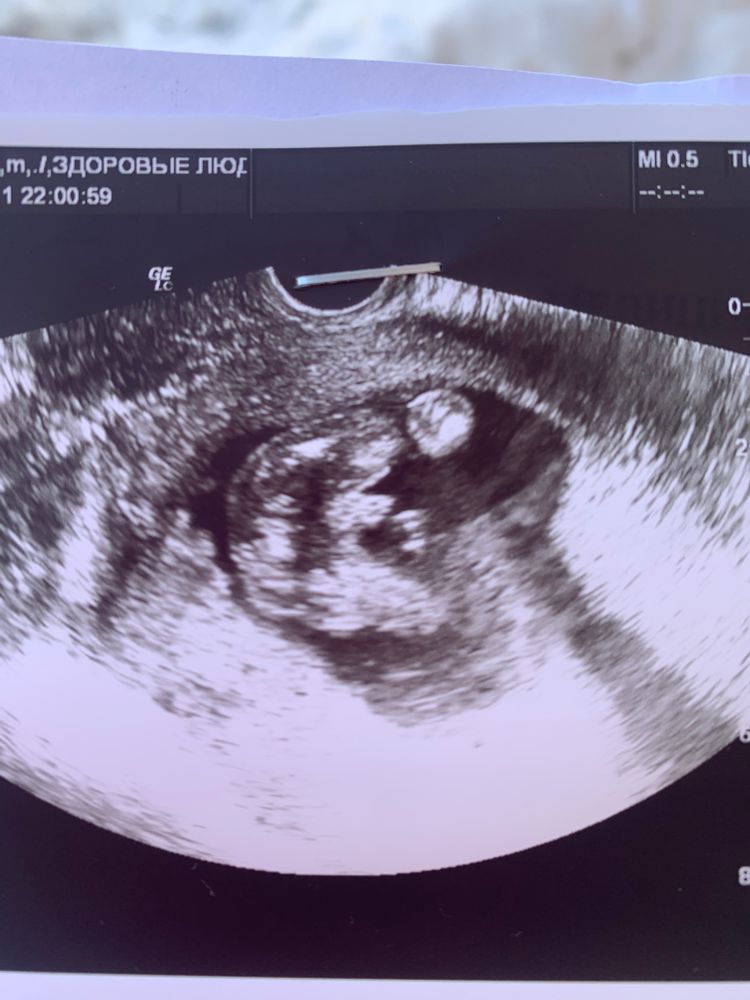

Марина BG, мы ждём второго парня ))вот меж ножек очевидно парень 😀 Изображение